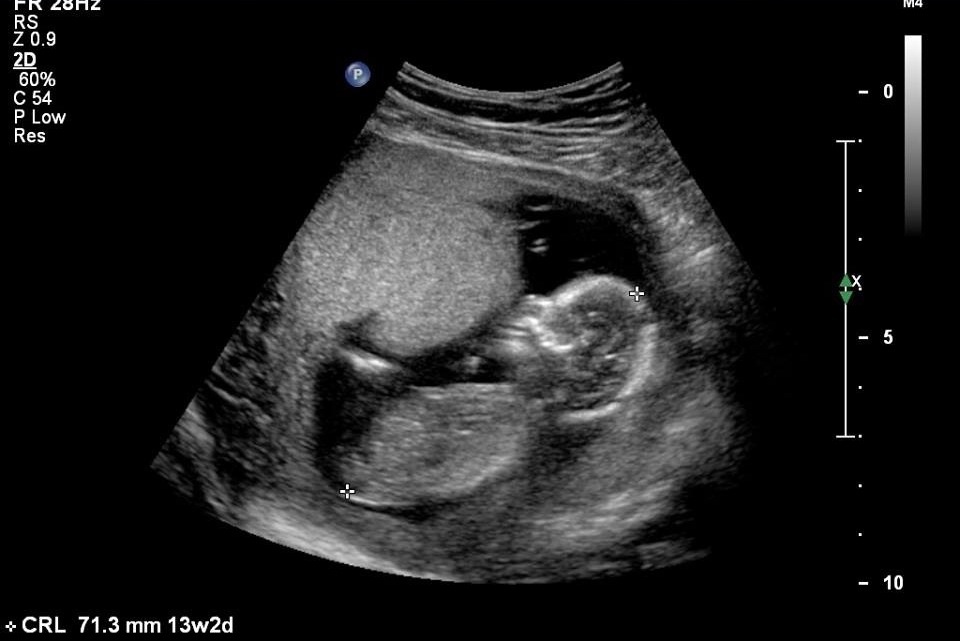

Had my scan today and I thought I was 12 weeks 5 days but ended up measuring 13 weeks 2 days... My uterus was contracting so baby was squashed and tech couldn't get any good pics! My scan ended up going for 1.5 hours!! The tech guessed girl but told me not to go shopping just yet and while in the scan I saw the all famous white line quite a few times but didn't get a pic :( the tech was so patient and tried everything so she could get the proper nuchal measurements so I didn't want to ask for

Nub too when baby was being so naughty lol... Here is the best pic I have... Skull and nub theory guesses appreciated :)

I think girl. When I zoom in, I can see a straight nub. Baby is a bit curled. But I still vote girl.

sorry I cant guess of the nub in this one but for fun ill guess girl from the skull xxxx